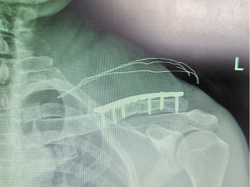

小周父母实在是发愁,到处打听,了解到了我院骨科可以进行微创手术治疗,切口小,恢复快,于是将孩子带到我院就医。我院骨科丁晔医师查看后,对患者采取微创闭合复位经皮弹性髓内钉内固定术。手术属于微创手术,仅需0.5cm的小切口从锁骨远端或锁骨近端为进针点,利用特殊器械及正骨手法,然后用弹性髓内针在锁骨髓腔内穿针固定,可以让骨折的锁骨恢复到正常形态和功能。小周的手术非常成功,患者家属很满意,悬着的心也终于放下了。

一0.5cm大小的微创切口

微创髓内针固定

微创手术治疗的优势:该方法最大限度地降低了软组织的损伤,对骨折端周围组织及血运破坏极少,因其切口小、创伤小、功能恢复快、外形更为美观、并发症发生率低。术后基本上不会留下瘢痕,尤其对于爱美的女士,病人满意度高。